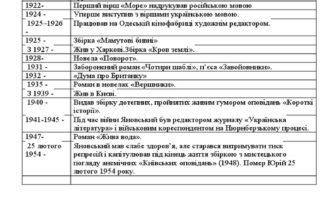

Перше — фізичні наслідки

Коли нерв вже зник — зуб стає “неживим”. Ну, не завсім бездушним, але і не повноцінно функціонуючим. Без кровообігу, він буде більш уразливим до розколювання. Будуйте плани на реставрацію!

І ще: зуб може змінити колір. Це не сюрприз, а реальність — без кровопостачання він може стати темнішим. Звичайно, не всі хочуть ходити з золотими коронками, тому існують різні методи, аби повернути йому природний вигляд…

Життя після видалення нерва

І тут вся правда: зуб, без свого власного “живлення”, потребує підвищеної уваги. Як у старшій родичці, у якої вже все не те. На нього не можна просто забути, інакше може вихопити таку ж мігренозну «радість», як і при звичайному карієсі.

| Можливі проблеми | Профілактика |

|---|---|

| Потемніння зуба | Відбілювання |

| Крихкість | Реставрація, коронки |

| Переінфекція | Регулярні огляди |

Психологічний аспект

І хто б міг подумати? Але так, може бути страх лікарів чи навіть самих відчуттів після процедури. Комусь від однієї думки запаморочиться. Тому моральна підготовка так само важлива, як і готовність піти на сеанс до холистичного терапевта.

Ще трохи про майбутнє вашого зуба

Після того, як нервова система зуба вже ні на що не здатна, ви отримуєте зуб без “бунтаря”. Але пам’ятайте, що це як мати машинку без двигуна — їде, але ж не дуже далеко. Догляд — ось що врятує ваш зуб від можливої передчасної втрати.